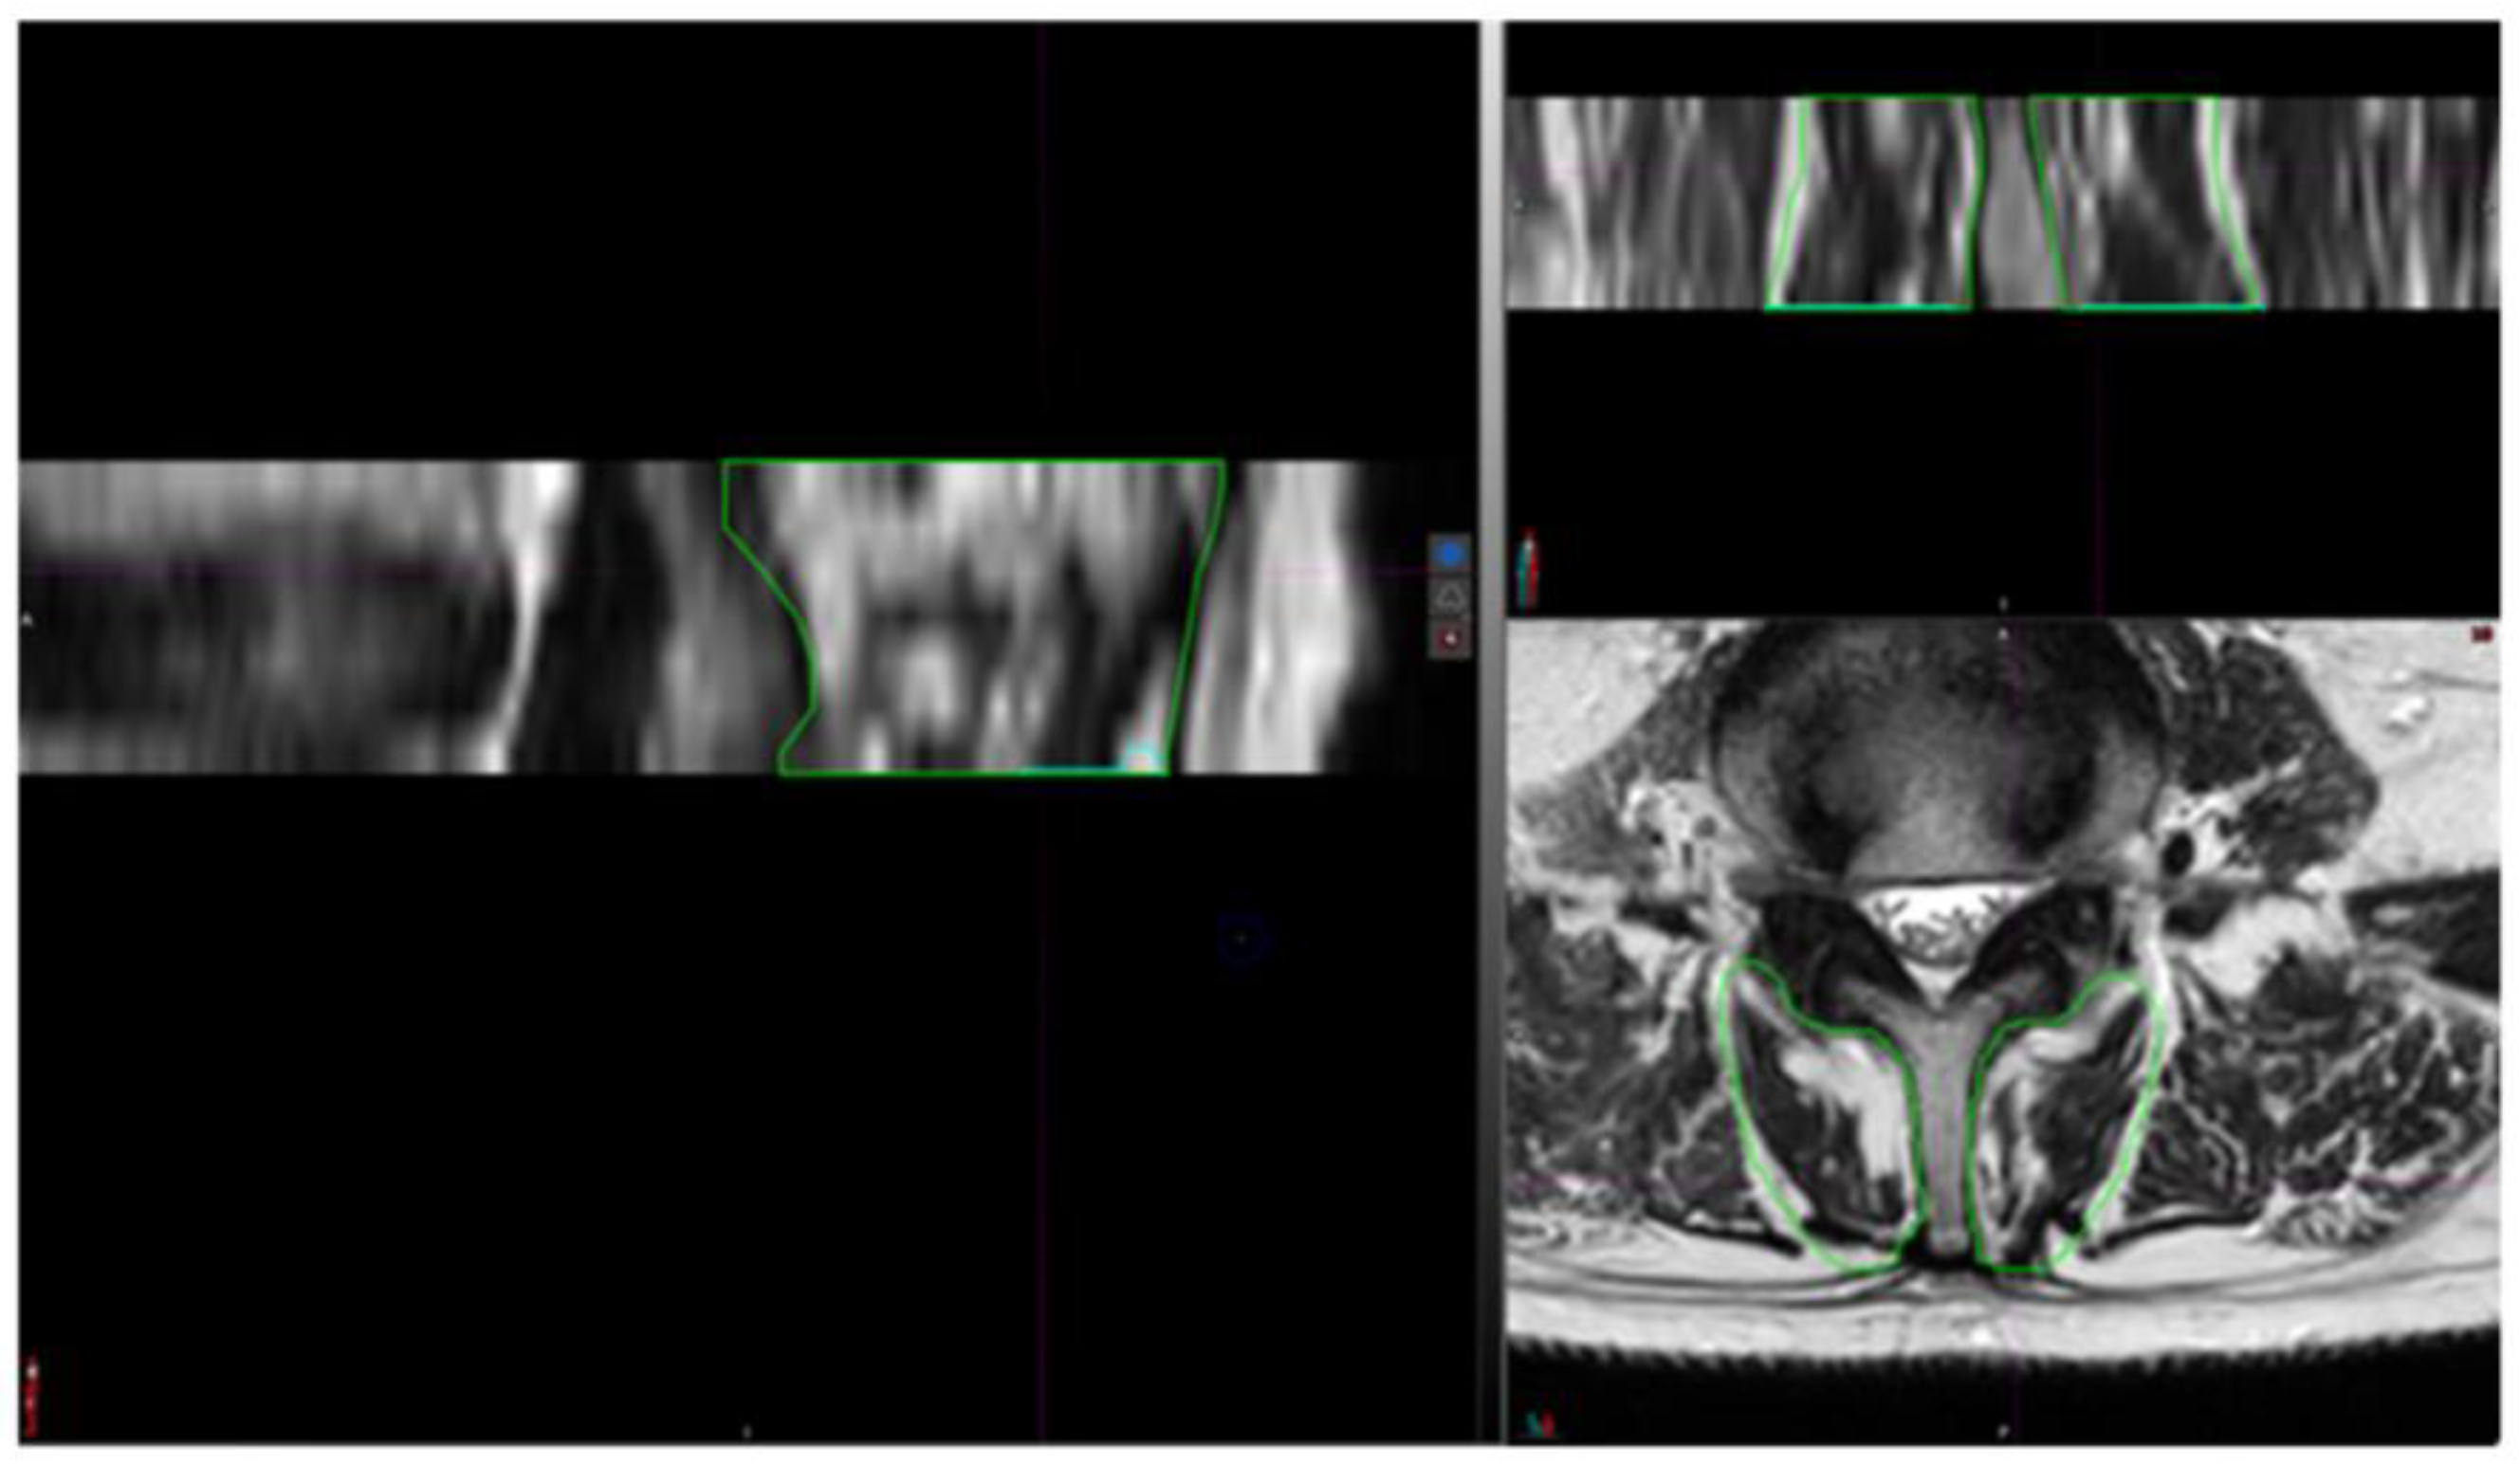

2.3. Segmentation Composition Analysis

3.3. Reliability Analysis